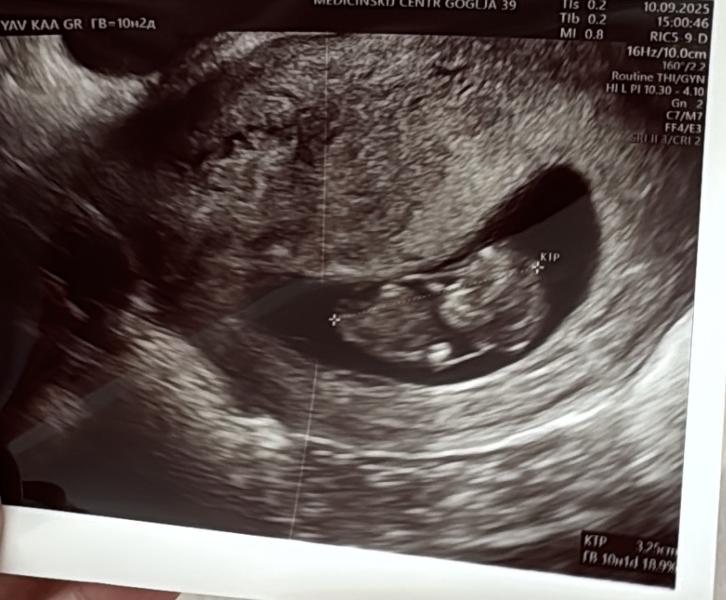

Сходила на узи, уже прям человечек целый 🥹 ручки ножки, всё есть ♥️ Хотя две недели назад ещё было что-то невнятное 🤣 все хорошо отслоек нет, соответствует сроку ♥️

Правда отвернулся спиной и спал, разбудить не смогли, поэтому фото со спины 🤣